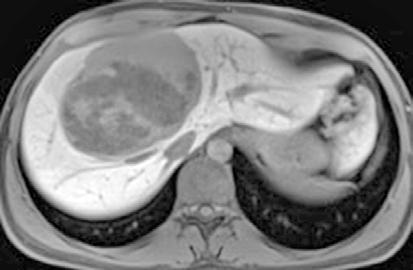

la hepática derecha y una rama más distal de la hepática izquierda, preservándose los segmentos II y III. (Figura 3)

Figura 3.

Angiografía previa a la embolización con micropartículas. A través de la femoral, accedemos a la aorta (Ao). De la aorta accedemos a la arteria mesentérica superior (AMS), de donde sale en este caso la arteria hepática (AH). Se divide en arteria hepática derecha (AHD) y arteria hepática izquierda (AHI). Se emboliza la AHD y una rama distal de la AHI. Vemos cómo ambas ramas dan abundantes ramas que irrigan la lesión.